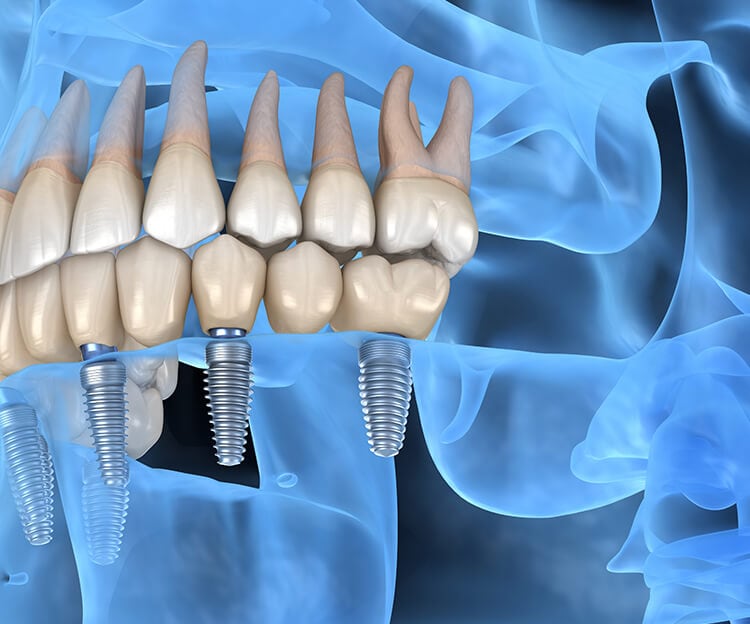

Straumann Dental Implants

We exclusively use Straumann Dental Implants, the world's leading implant system trusted by dental professionals globally. With over 60 years of innovation and research, Straumann implants offer superior osseointegration, long-term stability, and proven success rates. These premium Swiss-engineered implants provide the most reliable foundation for permanent tooth replacement, ensuring your investment in your smile lasts a lifetime.